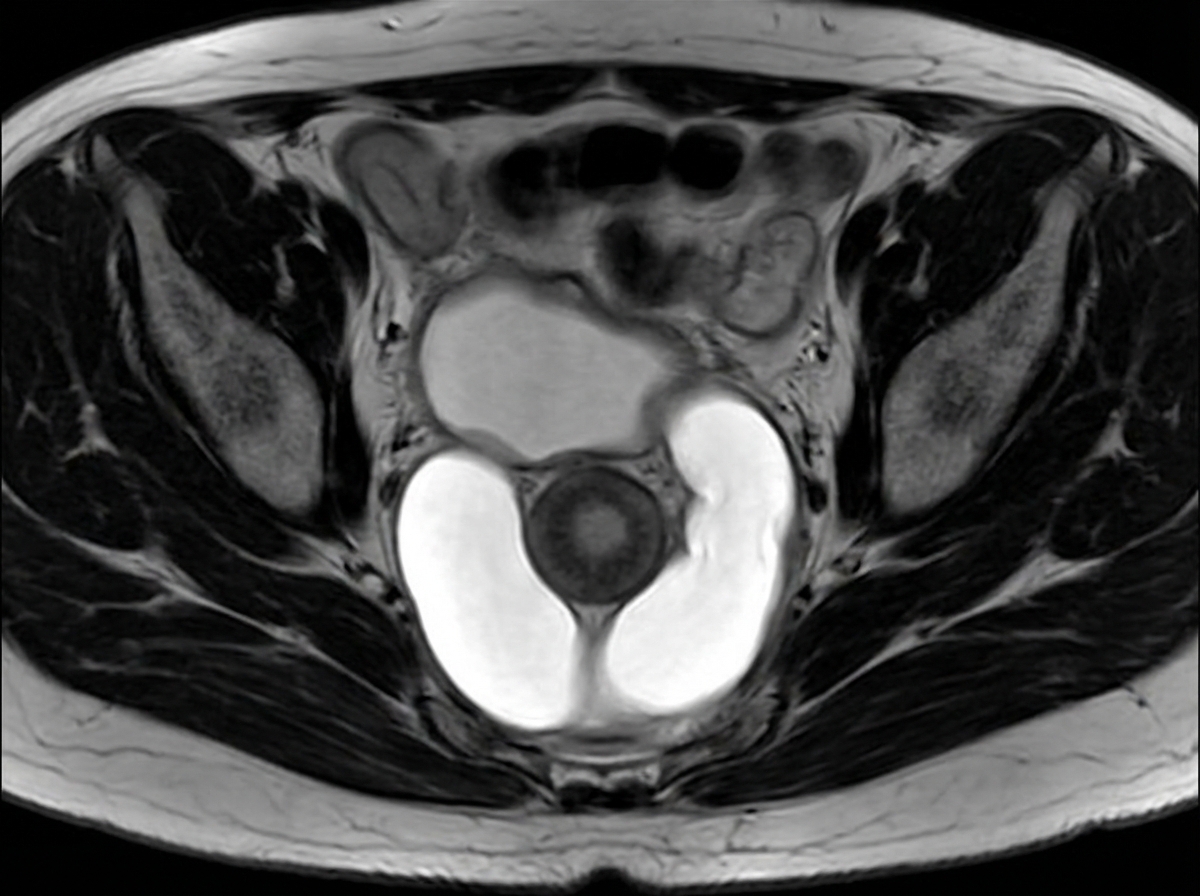

A female patient presents with post-void dribbling, recurrent urinary tract infections, and a tender anterior vaginal wall mass. Her MRI pelvis is shown in the image. What is the most likely diagnosis?

Explanation: ***Urethral diverticula*** - The classic triad of **post-void dribbling**, **recurrent UTIs**, and a **tender anterior vaginal wall mass** is pathognomonic for urethral diverticulum. - MRI typically shows a **fluid-filled cystic structure** adjacent to the urethra, which matches the clinical presentation. *Vesicovaginal fistula* - Presents with **continuous urinary leakage** into the vagina, not post-void dribbling. - Typically associated with **obstetric trauma** or surgical complications, causing constant wetness rather than a palpable mass. *Post-partum hemorrhage* - Occurs within **24 hours of delivery** and involves **excessive bleeding**, not urinary symptoms. - Characterized by **blood loss >500ml** (vaginal delivery) or **>1000ml** (cesarean), unrelated to urinary tract pathology. *Pelvic organ prolapse* - Involves **descent of pelvic organs** (bladder, uterus, rectum) into or beyond the vaginal introitus. - Symptoms include **pelvic pressure** and **bulging sensation**, not the specific triad of urethral diverticulum.